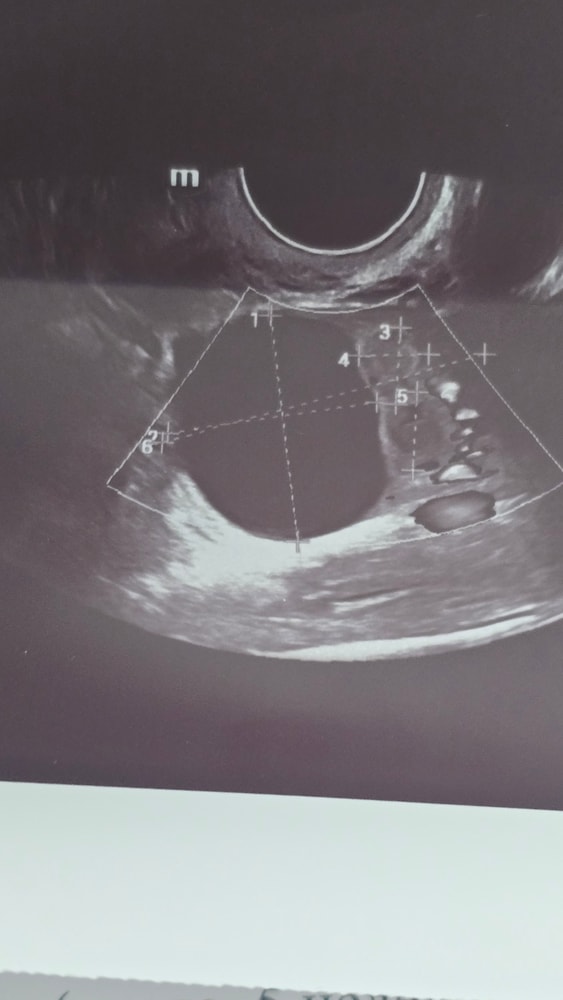

Очередной кринж , киста? Шансов нет? 😖

Отмените дюфастон, с врачом поговорите. Это от дюфастона киста. Но она всего на 9 мм больше верхней границы фолликула (до 20 мм). В следующий цикл бпз дюфастона вполне возможно её уже не будет

Да, вопрос киста жт или фолликулярная ? Прлнстерон может сдерживать О, и именно поэтому его и назначают пить после свершившейся О

Екатерина , фолликулярная, ну я сама виновата конечно , что начала дюфастон пить, но просто реально не думала, что что-то вырастет. Теперь то отменять дюф?

Ангелина, тут пару дней осталось, я бы отменила. Кстати это громадина, у меня вырос за цикл 5,5 см в диаметре

Изображение

Ангелина, это киста желтого тела ?

Аня, да нет, фолликулярная вроде